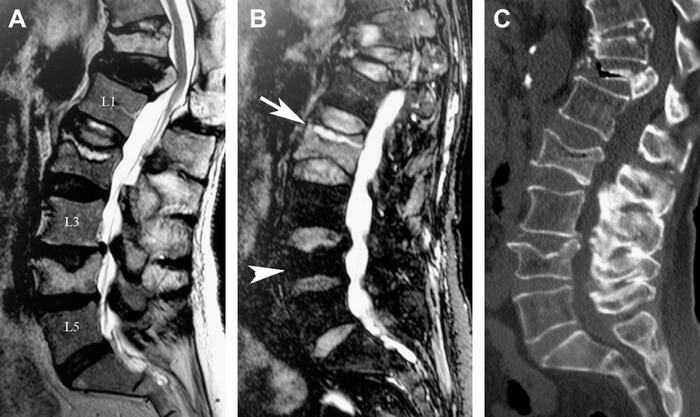

Η διάγνωση γίνεται με απλή ακτινογραφία όταν υπάρχει ήδη σημαντική καθίζηση του σπονδύλου ή με μαγνητική τομογραφία που επιβεβαιώνει ότι ένας παραμορφωμένος στην ακτινογραφία σπόνδυλος έχει υποστεί πρόσφατο κάταγμα. Ο ορθοπαιδικός χειρουργός, λαμβάνοντας το πλήρες ιστορικό του ασθενούς, θα του προτείνει την αγωγή που ενδείκνυται για την περίπτωσή του, συντηρητική -η οποία σε κάποιες περιπτώσεις είναι αποτελεσματική- ή χειρουργική.